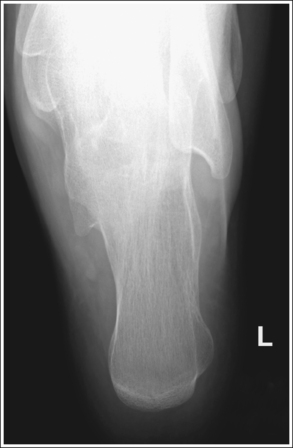

The talocalcaneal joint is demonstrated as an open space, and the calcaneal tuberosity is demonstrated without distortion.

• The talocalcaneal joint space is demonstrated as an open space, and the calcaneal tuberosity appears without distortion, when the correct central ray angulation and foot position are used. For a patient who has foot mobility, place the foot in a neutral-vertical position and direct a 40-degree central ray angulation toward the plantar foot surface (Figure 6-35). This positioning places the central ray parallel with the talocalcaneal joint space and perpendicular to the calcaneal tuberosity (Figure 6-36).

• Compensating for plantar-flexed or dorsiflexed foot. When the patient's foot is dorsiflexed beyond a 90-degree position with the lower leg or is plantar-flexed, the central ray needs to be adjusted to maintain its accurate position with the calcaneal joint space and tuberosity. If the patient's foot is dorsiflexed beyond the vertical position and a 40-degree angulation is used, the calcaneal joint spaces would be obscured and the tuberosity elongated (Figure 6-37; see Image 23). In this situation the central ray angulation should be decreased to maintain accurate central ray alignment. If the patient's foot is plantar-flexed and a 40-degree central ray angulation is used, the calcaneal joint space is obscured and the tuberosity foreshortened (see Image 24 and Figure 6-38). In this situation the central ray angulation should be increased to maintain accurate central ray alignment. The angulation required for each of these situations can be estimated by locating the base of the fifth metatarsal and the distal point of the fibula. The fifth metatarsal base is palpable on the lateral foot surface approximately halfway between the ball of the foot and the heel. Once these structures are located, angle the central ray parallel with an imaginary line drawn between them. When the axial calcaneal projection is taken with the foot in plantar flexion and the central ray is angled as just discussed to demonstrate the talocalcaneal joint space, the calcaneal tuberosity will be elongated because of the acute angle created between the central ray and IR (see Image 25).

The second through fourth distal metatarsals are not demonstrated on the medial or lateral aspect of the foot, respectively.

• To prevent calcaneal tilting, place the patient supine on the imaging table, with the leg fully extended and the foot dorsiflexed until its long axis is placed in a vertical position, without medial or lateral rotation or foot inversion or eversion. If the ankle is internally rotated or the foot inverted, the first and second metatarsals are demonstrated medially. If the ankle is externally rotated or the foot everted, the fourth and fifth metatarsals are demonstrated laterally (see Images 25 and 26).